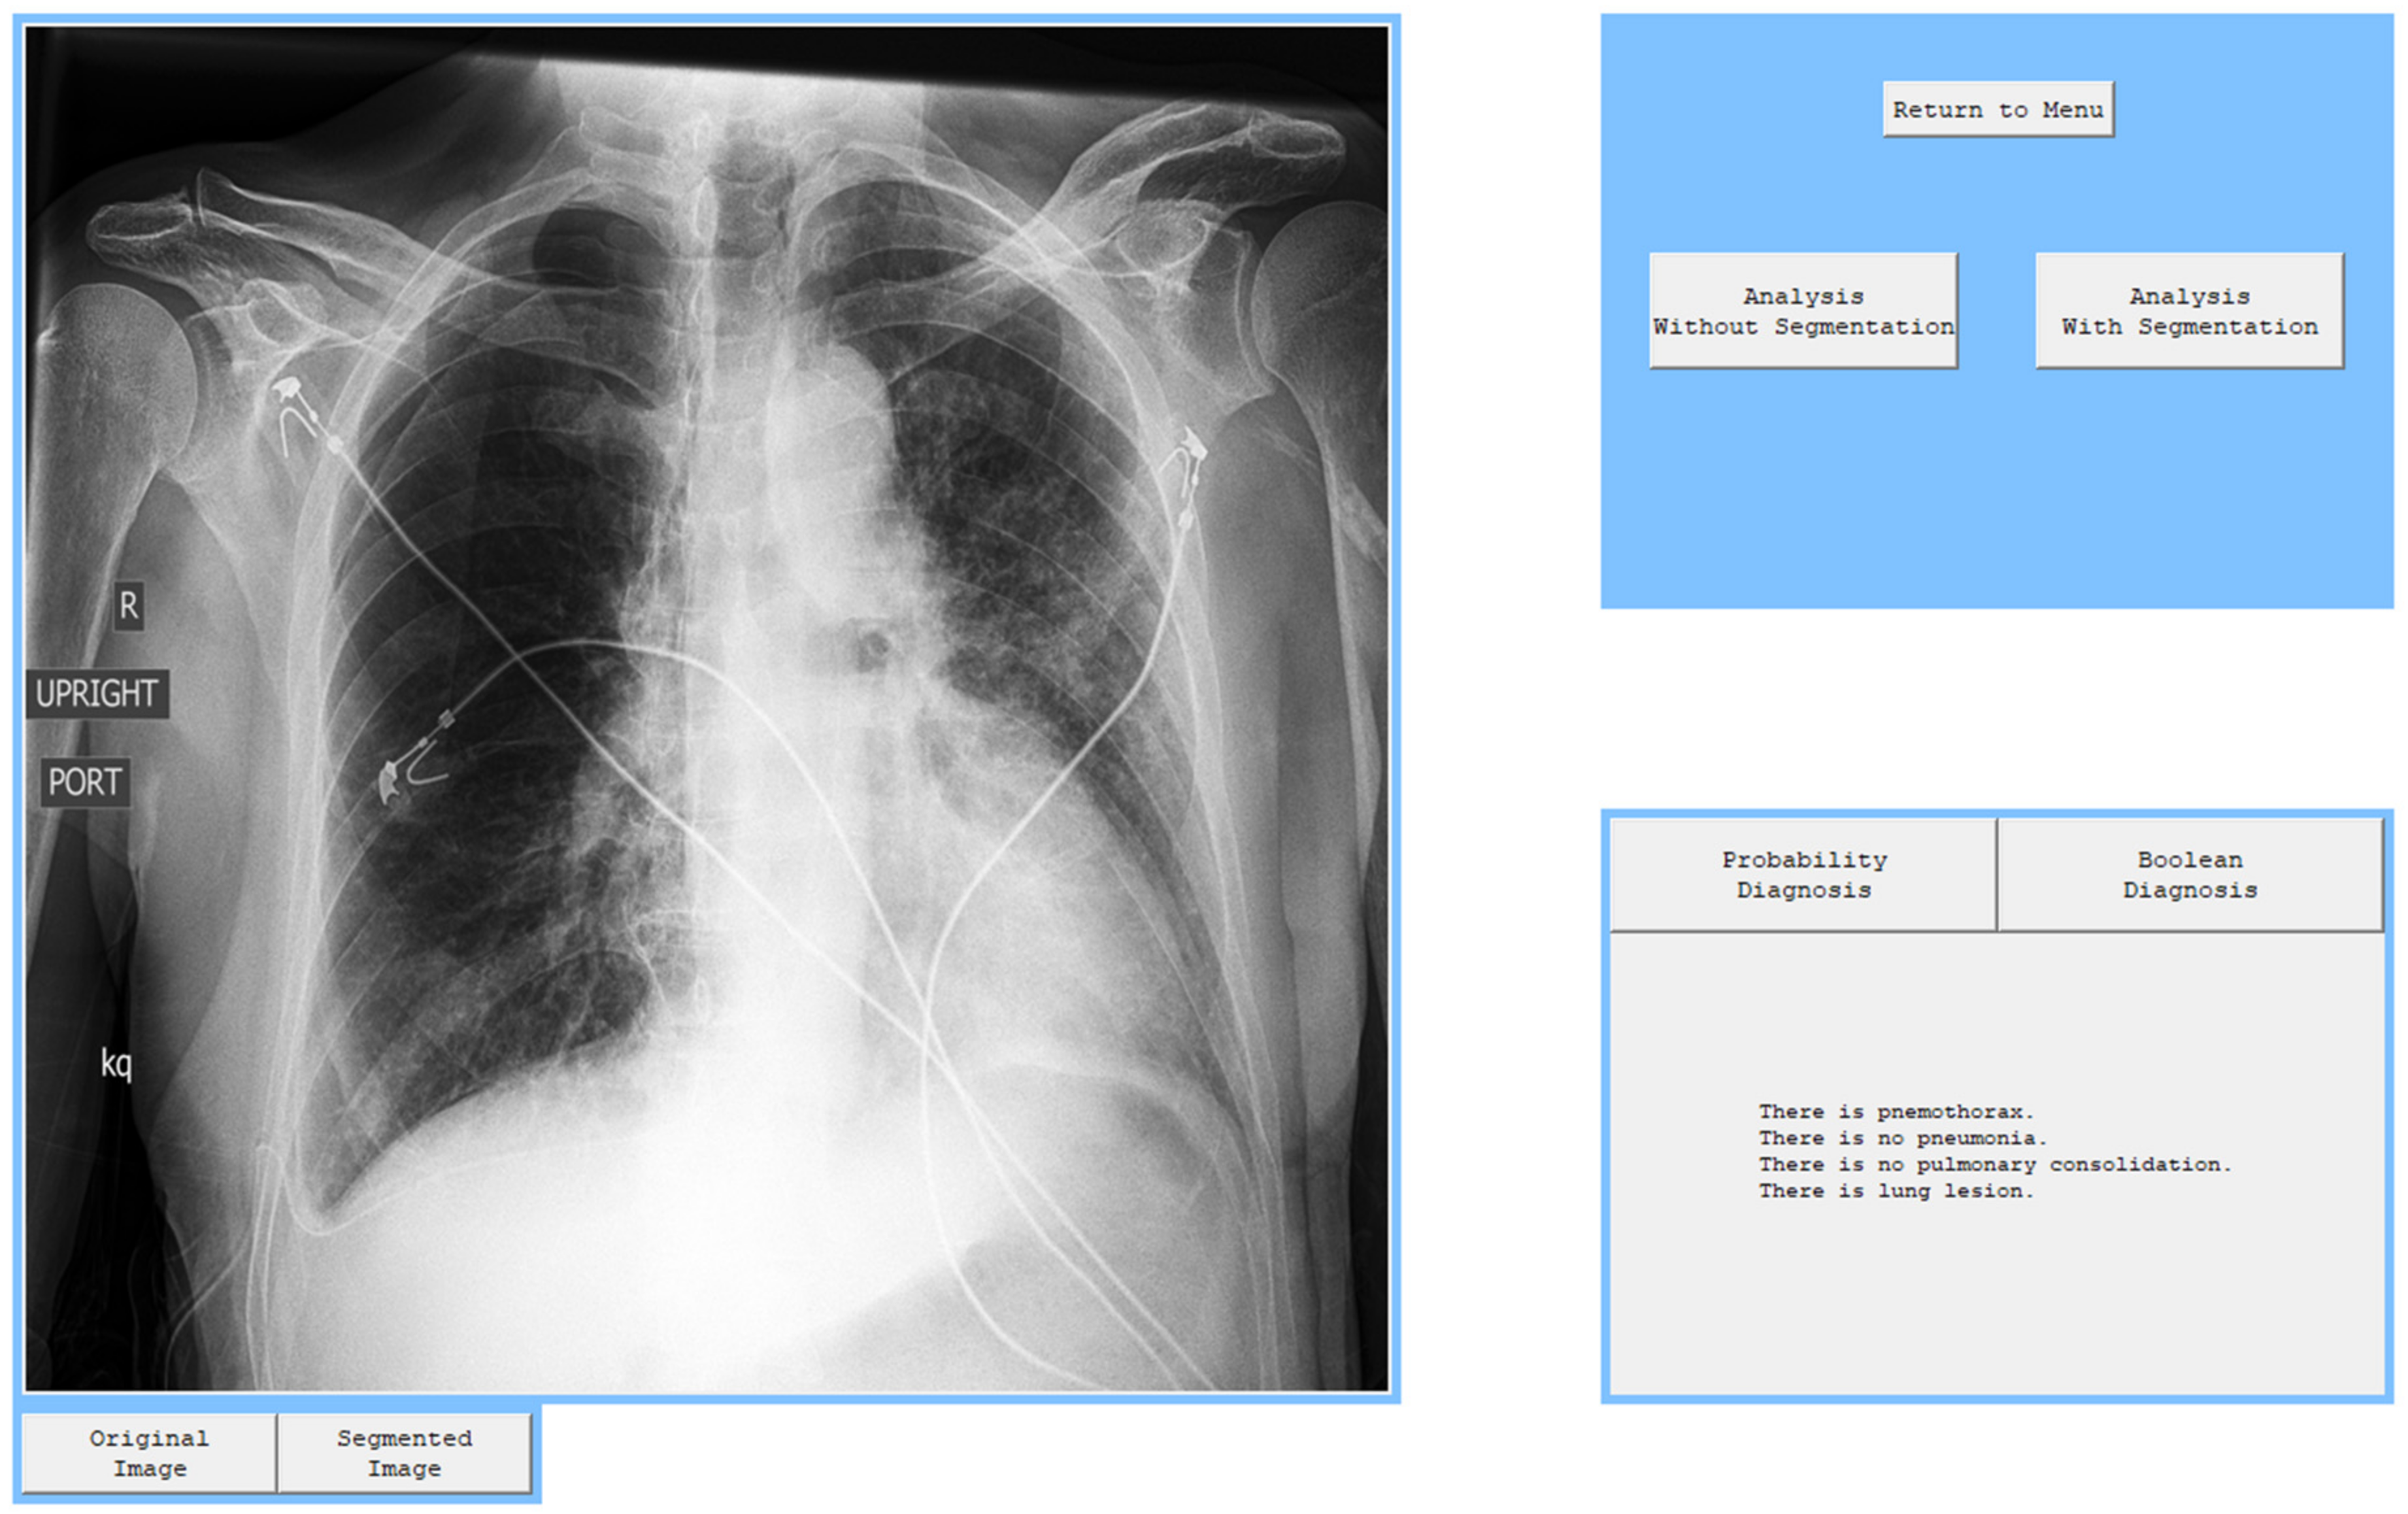

In order to present the operation of the models, a window application with basic functionalities was created in accordance with the MVC pattern architecture. It allows the user to load an image and analyze it with all four algorithms. It also performs an image segmentation and presents it on screen. All four diagnoses are performed separately in series and are independent, which means that the bad performance of one of them does not affect the performance of the other one.

After every model was tested separately, an attempt was made to check how all models combined into one program would diagnose all four pathologies. On the graphical user interface, it can be seen that there are two possible analyses, but as it was mentioned before, analysis with segmentation has considerably better results, so analysis without segmentation should be used when radiologists estimate that there is significant information outside the segmentation. There are also buttons that allow the user to switch between diagnoses presented in the form of probability and the boolean diagnosis. The application also provides buttons that can switch the view from segmented lungs to the original image.

The program works smoothly and diagnoses pathologies correctly on the testing set. Sample diagnoses were presented in Figure 8, Figure 9 and Figure 10. The radiologist can use this application to analyze one or many images very quickly and obtain one specific diagnosis. If they accept this diagnosis, they can go on and check the next patient and if they have doubts, they should check their diagnosis again and maybe change their verdict. As it is presented, the segmentation process also works without problems and shows the image that can help the radiologist to focus attention on what is essential and not become distracted with worthless information.

Figure 10. Diagnosis of patient with pneumothorax and lung lesion.